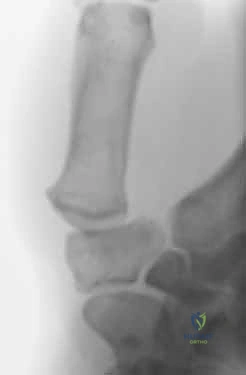

- Plain Radiographs: These are the cornerstone. Obtain posteroanterior (PA), lateral, and oblique views of the affected digit. These are usually sufficient for diagnosis.

- Look for joint space narrowing, osteophytes, subchondral cysts, erosions, and subluxation.

- In psoriatic arthritis, look for "pencil-in-cup" deformities or severe bone resorption (arthritis mutilans).

- Assess bone stock, quality, and size, which are crucial for determining the optimal fixation type.